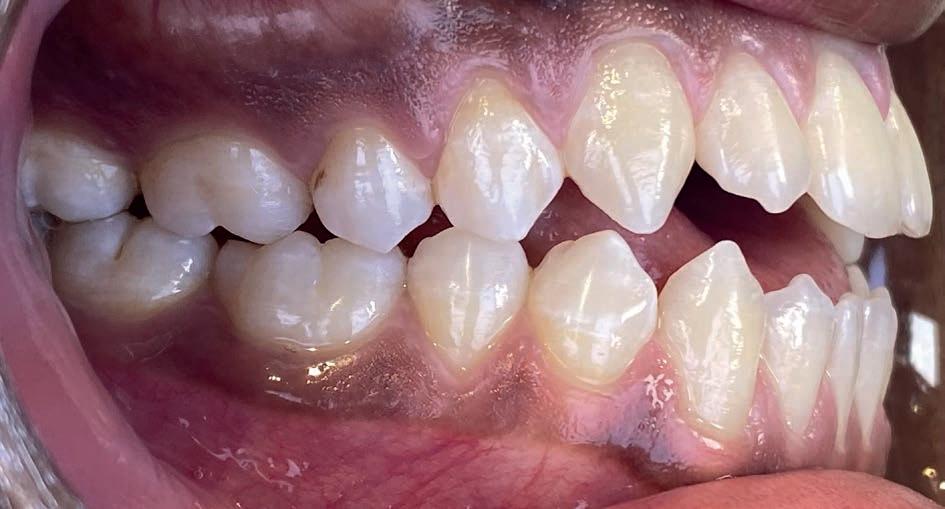

Casus: Jorn

Niet-chirurgische correctie van een Klasse III-relatie

Patiënt: Jorn (18 jaar)

Behandelduur: 15 maanden

Behandeling: Damon Ultima brackets en elastieken

Jorn en zijn vader kwamen via Google bij Clover

Orthodontie terecht, nadat hij elders een chirurgisch behandelvoorstel had gekregen. Als actieve voetballer paste een operatie niet in zijn leven. Hij presenteerde zich met een skeletale Klasse III-relatie, anterieure kruisbeet, negatieve sagittale overbeet en een concaaf profiel.

Behandelstrategie

Er werd gekozen voor een behandeling met Damon Ultima brackets en een strak gepland elastiekprotocol. Vanaf het begin droeg Jorn Klasse III-elastieken om de sagittale discrepantie te corrigeren. Dankzij de precisie en lage frictie van Damon Ultima konden we transversaal én sagittaal corrigeren zonder chirurgische ingreep.

Het eindresultaat bestond uit een stabiele Klasse I-occlusie met een duidelijk verbeterd profiel. Er zijn geen extracties of chirurgische ingrepen uitgevoerd. Voor de retentie werd gekozen voor vaste spalken in combinatie met nachtbeugels, om het bereikte resultaat langdurig te behouden.